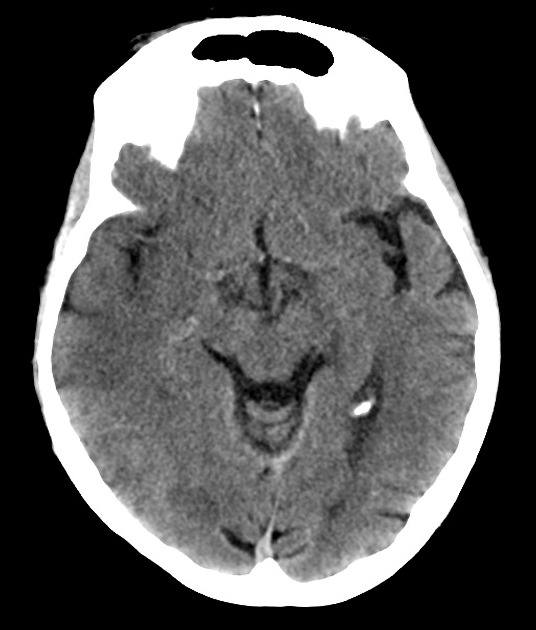

Nhồi máu não

» Thông tin: Nam giới – 60 tuổi.

» Lâm sàng: Đau đầu + Liệt nửa người trái / NIHSS 18 điểm.

# Nhồi máu sớm bán cầu phải thuộc vùng cấp máu ĐM não giữa / Huyết khối ĐM não giữa phải.